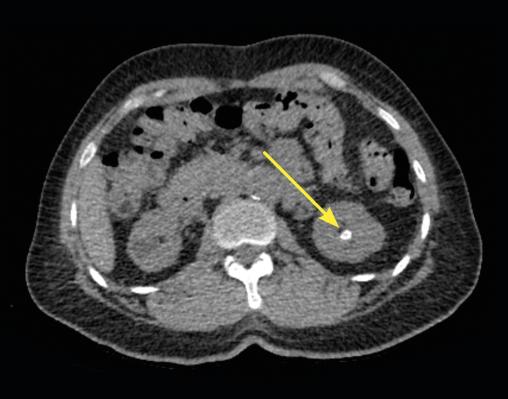

En raison de la taille du calcul, qui expose à un risque de migration symptomatique urétérale, l’ablation urétéroscopique est décidée et réalisée de manière élective une fois le traitement anticoagulant de l’embolie pulmonaire terminé. L’intervention se déroule sans complication (lithotripsie au laser in situ et extraction du calcul) [fig. 3]. Le patient est rentré chez lui vingt-quatre heures heures plus tard.

L’analyse du calcul par spectrophotométrie infrarouge révèle une formation étonnante, entièrement composée de sulfate d’atazanavir, un inhibiteur de protéase, utilisé en association avec du ritonavir. Cette origine médicamenteuse exclusive, extrêmement rare, a entraîné un signalement de pharmacovigilance pour effet indésirable auprès de Swissmedic(autorité suisse d’autorisation et de surveillance des produits thérapeutiques). Le patient avait débuté cet antirétroviral il y a onze ans, l’avait pris pendant quatre ans à une dose quotidienne de 300 mg, puis l’avait arrêté il y a sept ans.